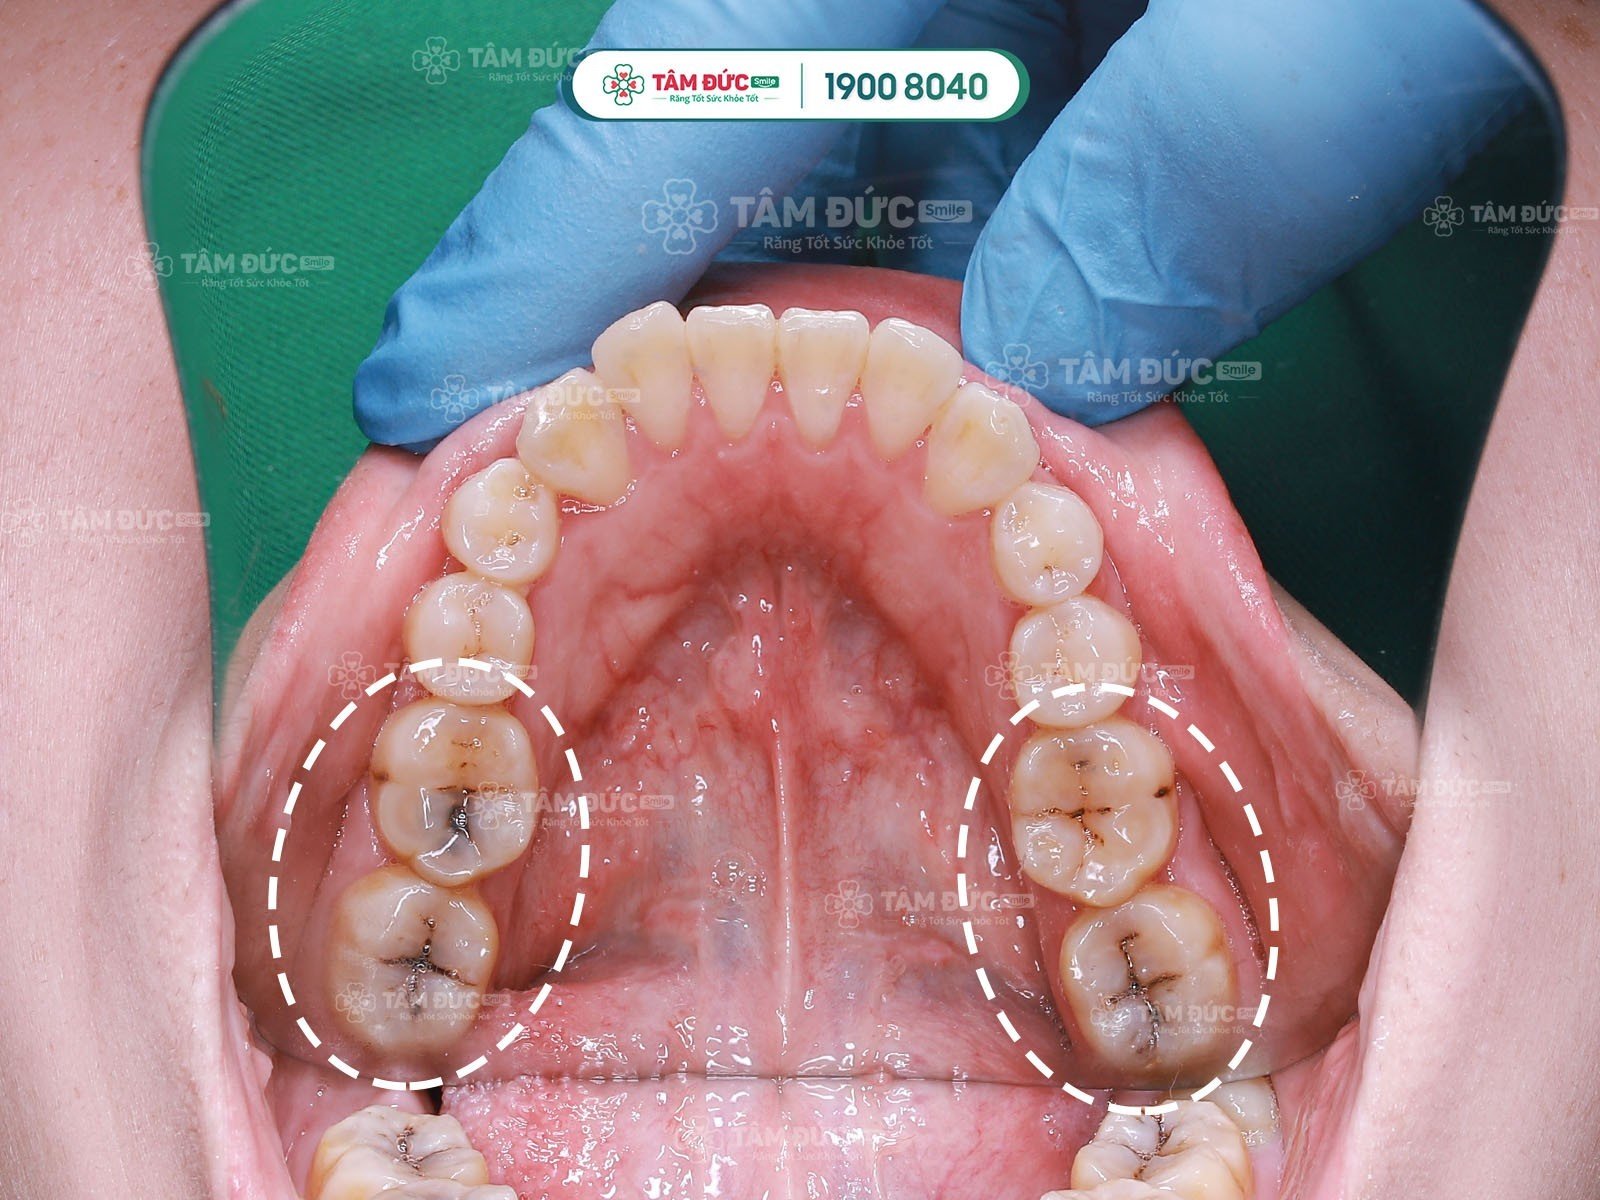

chữa tuỷ răng

chữa tuỷ răng sâu

Các trường hợp răng cần chữa tuỷ